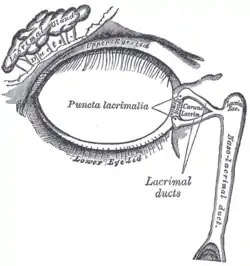

The tarsi and their ligaments. Right eye; front view The lacrimal apparatus. Right side

The lacrimal apparatus. Right side Extrinsic eye muscle. Nerves of orbita. Deep dissection